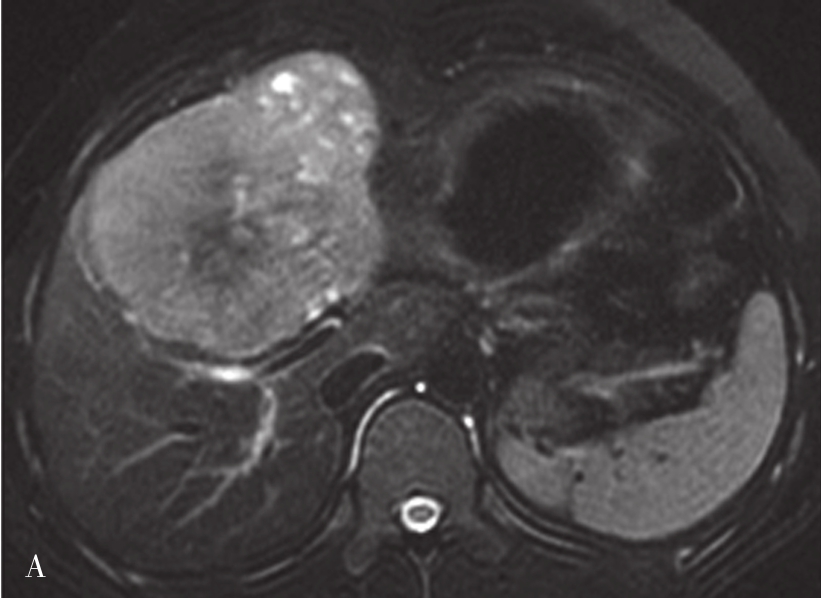

图5-21-42 HCC患者的MRI图像

A.T 2 WI脂肪抑制图像,可见肝右前叶内较大略高信号为主的病灶,内有点状更高信号影及中央低信号区,边界较清楚;B.600s/mm 2 时DWI图像,可见病灶为略高信号为主,中央略低信号;C.脂肪抑制图像,可见病灶为低信号影,边界较清楚,其内有一高信号影(箭头),为出血信号;D.增强扫描动脉期图像,可见病灶内轻微强化;E.可见门脉期图像病灶不均匀强化;F.可见延迟期图像病灶大部强化,中央无强化,假包膜清楚

HCC最常见的MRI表现为T 1 WI呈略低信号,T 2 WI呈略高信号,DWI呈高信号(图5-21-42)。有文献报道T 1 WI呈等信号者,多为分化较好的早期HCC,而脂肪变、出血、坏死、细胞内糖原沉积或铜沉积可导致病灶在T 1 WI上呈高信号,此外,在肝血色病基础上发生的HCC,由于肝实质在各脉冲序列图像上信号均很低,病灶一般都呈相对高信号。肿瘤假包膜可见于40%~70%的结节型和巨块型HCC。Gd-DTPA增强较为特征性的强化形式是对比剂“快进快出”,其原理为这些病灶70%的血供来自肝动脉,延迟相上出现宽0.5~3mm的包膜强化也颇具特征。采用特异性肝细胞摄取的对比剂,比如钆塞酸二钠(Gd-EOB-DTPA,普美显)不仅有其他钆类对比剂同样的动态增强外,在静脉注射10~30min内约有50%被正常肝细胞摄取,而不含正常肝细胞的HCC则很少或基本不摄取,而在肝特异性期呈低信号。有助于小HCC与肝硬化再生结节和其他良性病变的鉴别。大多数HCC在肝特异性期呈现相对低信号,但约10%的分化程度较好的HCC亦可呈等或高信号。